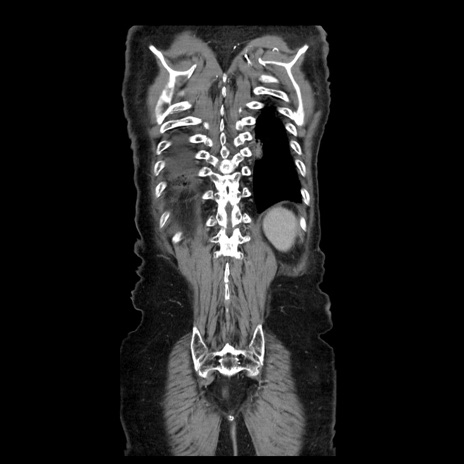

症例21(冠状断像)

【症例】70歳代男性

【主訴】腹痛

【現病歴】肝硬変・肝細胞癌にてかかりつけの方。約9時間前に食後より腹痛出現。症状が徐々に増悪し、嘔吐出現したため来院。

【既往歴】肝硬変、肝細胞癌(RFA、TACE後)

【身体所見】意識清明、表情苦悶様、BT 36℃、BP 129/78mmHg、P 88bpm、SpO2 97%(RA)、右上腹部から心窩部にかけて圧痛あり、反跳痛なし、筋性防御あり。

【データ】WBC 5800、CRP 0.16